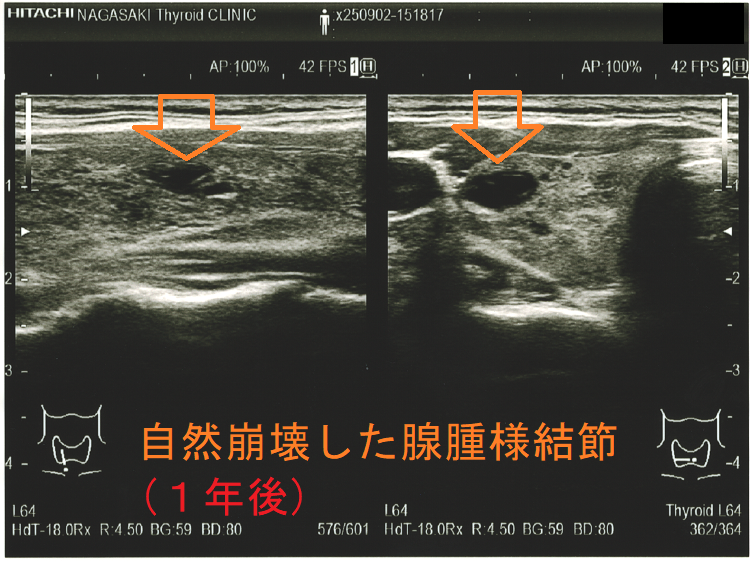

穿刺細胞診後内部融解

ケース①

ケース②